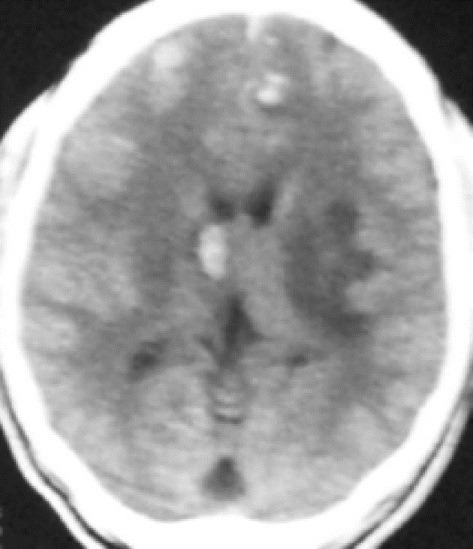

Figure 2.

Multiple hyperdense nodular densities due to cerebral granulomas in a patience with HIV/AIDS

Twenty-four patients (60%) were single and 12 (40%) were married. This agreed with the reports by other authors.4,19 All the patients presented with advanced diseases, with serious CNS complaints or symptoms that encouraged them or their relations to pay for the CT scan study. All the features which the patients presented with were serious neurological features making this group a highly selected group. The high cost of CT scan compared to the patients earnings, mean that only very serious symptoms and signs convinced the patient or relations to pay for the CT study.12,13 The features seen on CT scan showed that cerebral infarct-like lesions 14 (38.9%) were the most common findings on CT scan. These were moderate in size and multiple in majority of the cases. The next highest recorded finding was multiple ring-enhancing lesions with associated hypodense mass effect due to surrounding oedema. These lesions have many differential diagnosis including toxoplasmosis, lymphoma, tuberculosis, bacterial meningitis with cerebral abscess, progressive multifocal leucoencephalopathy, cytomegalovirus infection, and cerebral fungal infection and it is impossible to differentiate each of these as the cause in each case using computed tomography alone.20–22 Two or more of these causes of multiple ring-enhancing lesions could coexist. Biopsy for histology was not done because of the absence of facilities for this in our centre at that time. Three patients with single or multiple ring-enhancing lesions recovered following drug treatment for cerebral toxoplasmosis [Figures 1 and 4]. Coexistence of more than one cause of single or multiple ring-enhancing lesions could be responsible for incomplete response in other patients treated for cerebral toxoplasmosis. Other causes of ring-enhancing lesions could not be conclusively diagnosed. Cerebral atrophy (15.9%) was the third highest lesion noted. Multiple nodular lesions which were mostly hyperdense, suggestive of granulomatous lesions were seen in four patients (11.1%) [Figure 2]. Other lesions recorded are shown in the table. These findings are consistent with the report of other authors that the main diagnoses to exclude in patient with HIV/AIDS which led to request for brain CT scans were stroke, tuberculosis, toxoplasmosis and lymphoma.4,6,10,17,18 Cerebral infarct-like lesions [Figure 3], presenting clinically as stroke, is recognized as one of the radiological findings of many CNS conditions in patients with AIDS who develop focal mass-like effect and ring-enhancing lesions.21–27 In this study, brain mass lesion was seen in 11.1%. This finding agrees with the findings by other authors that brain mass lesions were seen in 10% of patient with HIV/AIDS.4,17–26,28

The importance of the study is that brain mass lesions in patients with HIV/AIDS were often caused by oedema of the CNS due to infections such as cerebral bacterial abscess, toxoplasmosis, tuberculosis, and other granulomatous lesions [Figures 1, 2 and 4]. The patients’ conditions could be improved by the relieve of the oedema with appropriate drug treatment of the causes.4,10,18,24,25 For instance, some of the patients with toxoplasmosis improved with the correct treatment for this condition in this study. CNS lymphoma and other noninfections conditions are however very difficult to exclude using imaging alone and thus biopsy for histology and other diagnostic investigations are invaluable where facilities are available.